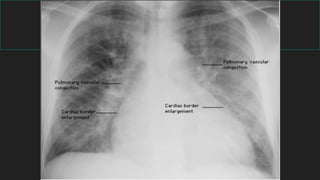

INSUFICIENCIA CARDIACA

Recuerde los 4 signos radiológicos:

 1) Lineas B Kerley

 2) Congestión peribronquial

 3) Liquido en las cisuras

 4) Derrame pleural

 CARDIOMEGALIA